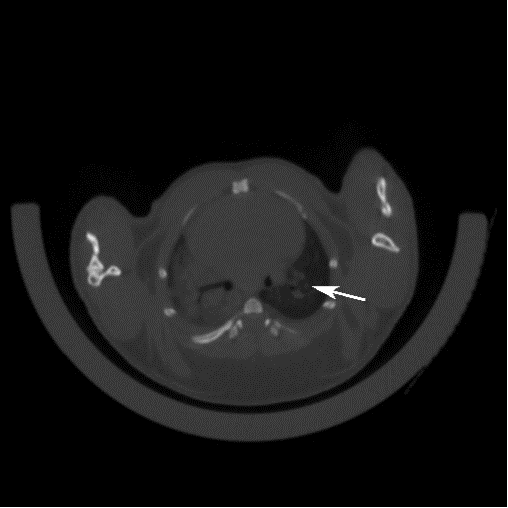

1 肺部CT檢測腫瘤的形成